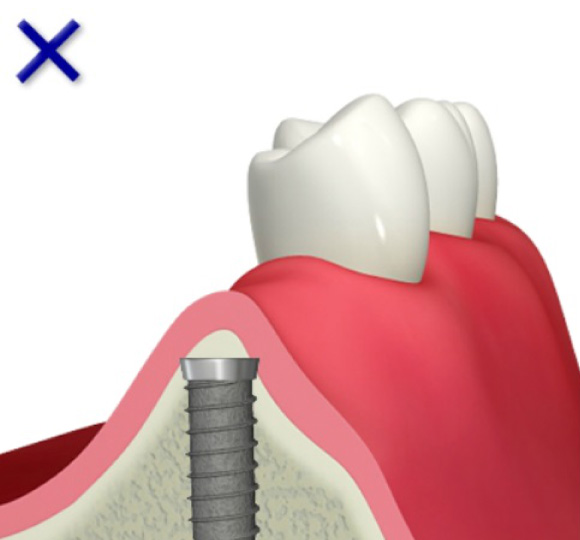

インプラントの欠点

■インプラントは骨にはしっかりくっ付きますが、歯茎にはゆるくしかくっつかないため、天然歯よりも若干、感染に弱い。

インプラントを支えるための歯槽骨が十分でないためインプラントはできません。

インプラントを支えるための歯槽骨が作られました。インプラントを埋入する事が出来ます。

GBR法